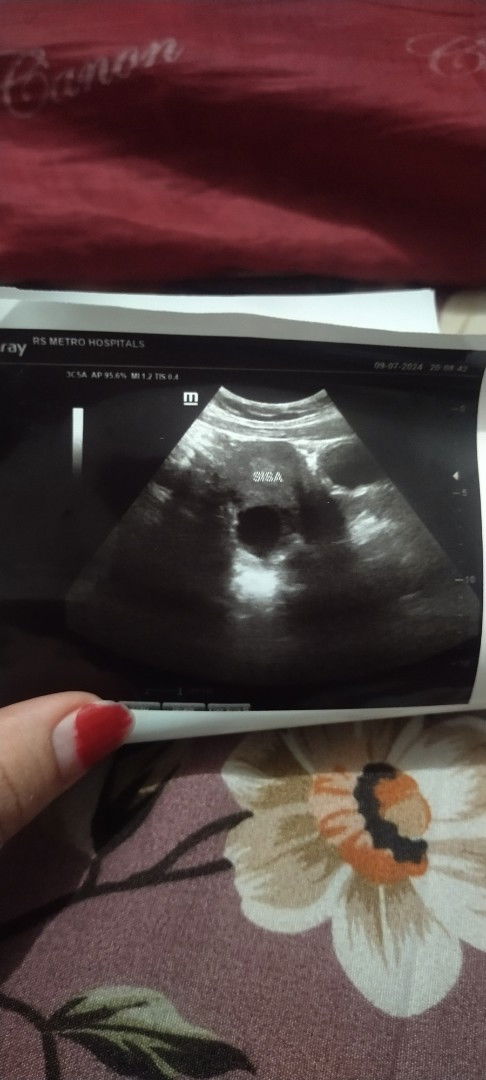

Ini hasil USG pertama aku pas usia kandungan 5week, cuma waktu USG dokternya bilang blom keliatan apa². Tapi yg lingkaran itu apa yaa? Soalnya waktu USG dokternya ga menjelaskan secara detail